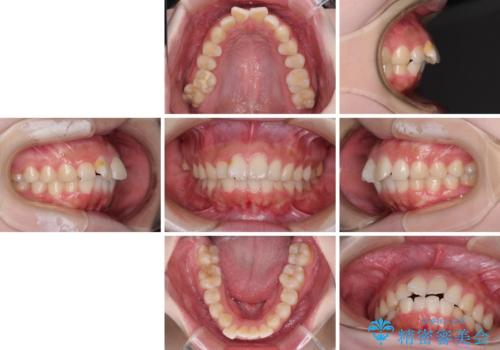

前歯のデコボコをインビザラインできれいに整える

- 前歯のデコボコと上下の隙間を気にして来院された患者様です。

前歯の捻れを改善するとともに、口元が少しでも引っ込むように治療計画を立て、仕上げることができました。

長時間の装着や、定期的な来院がままならず、想定よりも長期間の治療となってしまいました。